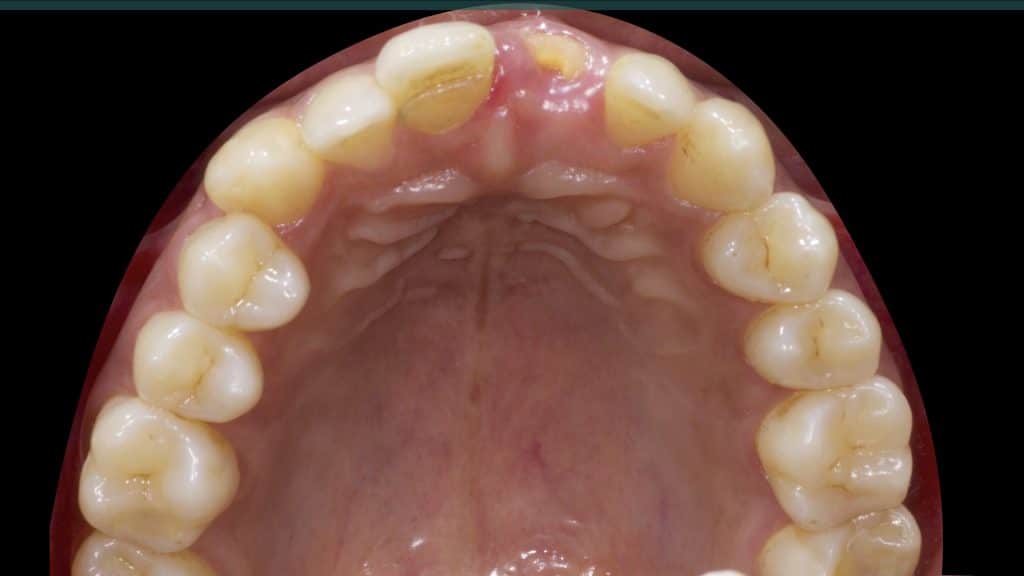

20 days post-op after suture removal